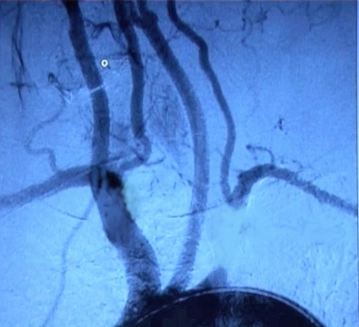

Angiografía por sustracción digital (DSA), angio-RM

• representación de la circulación supraaórtica incl. brazo y del circuito de robo